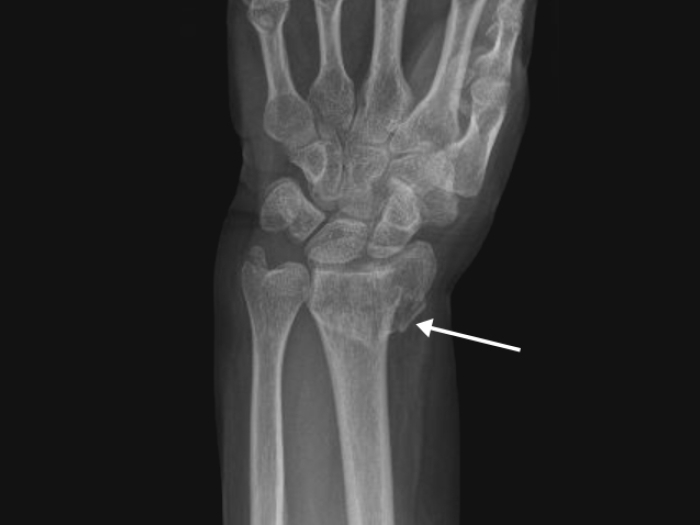

forearm wrist bone fracture with arrow pointing to it on xray

Personalized medicine, not X-rays, should guide common forearm fracture treatments in older adults

The new findings will guide future treatments of distal radius fracture.